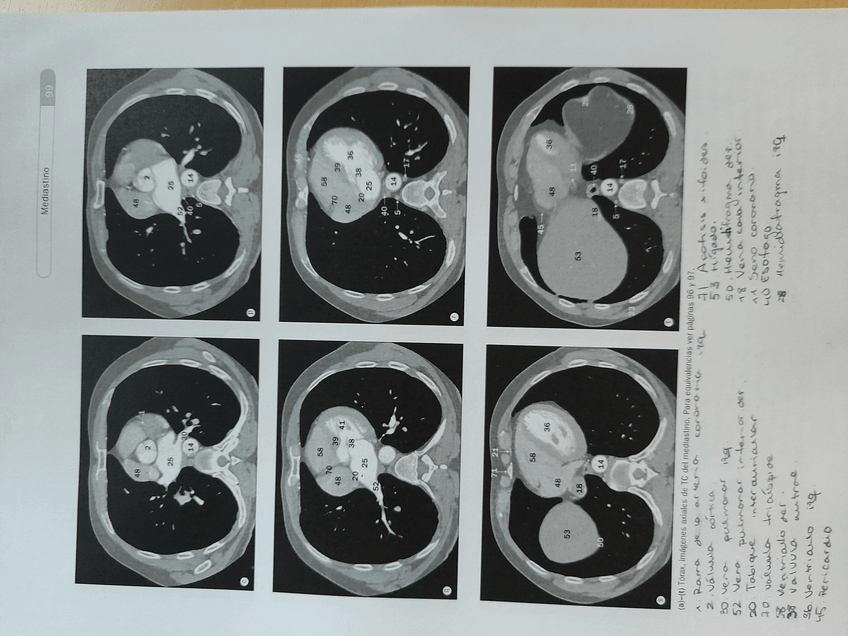

ANATOMIA

Columna, cintura, extremidades…